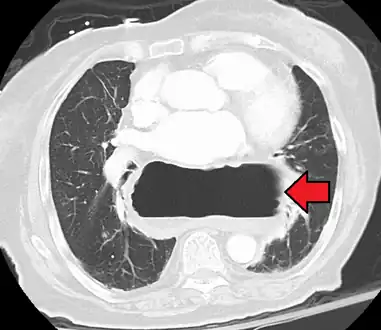

A large hiatal hernia on chest X-ray marked by open arrows in contrast to the heart borders marked by closed arrows

This hiatal hernia is mainly identified by an air-fluid level (labeled with arrows).